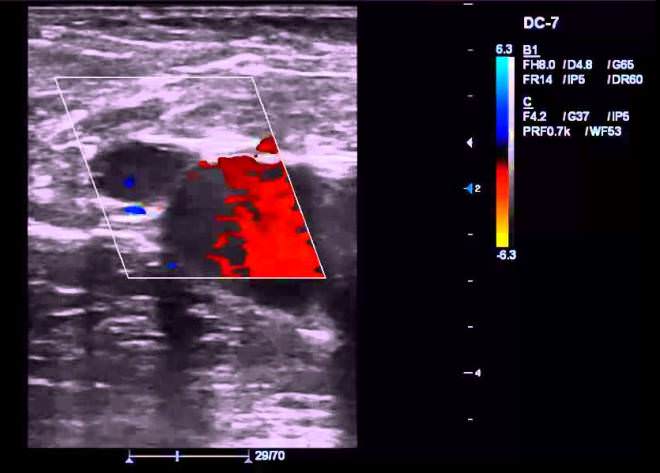

Научные достижения позволили создать аппараты, преобразующие сигналы датчиков в цветные изображения, изучаемые специалистами непосредственно на экранах мониторов. Более того, процесс пульсирующего кровенаполнения можно даже услышать в виде разных по интенсивности шумовых проявлений, свойственных сосудам.

Так цвет и звук позволяют осуществлять углубленные исследования кровотока, а значит, и вынести уточненный диагноз вероятного заболевания.

Оценивать проходимость вышеописанных структур удобнее всего при ангиосканировании, визуализирующем движение кровяных частиц. Так, тромбы и посттромботические элементы видны как неподвижные, гетероэхогенные плотные включения со свечением разной степени интенсивности.

Для получения дополнительных данных (при подозрении на внутрисосудистые патологии и слишком невысоких скоростях кровотока) рекомендуется применять энергетическое либо цветовое картирование.

Второй метод исследования сосудов конечностей – ангиосканирование. Оно дает цветное изображение, где также отображается скорость и направление кровотока, однако благодаря подсвечиванию изучить их можно более подробно.

Нередко подобное УЗИ бывает повторным, т. к. дает исчерпывающую информацию о состоянии кровотока, что позволяет врачу сделать окончательные выводы о диагнозе пациента.